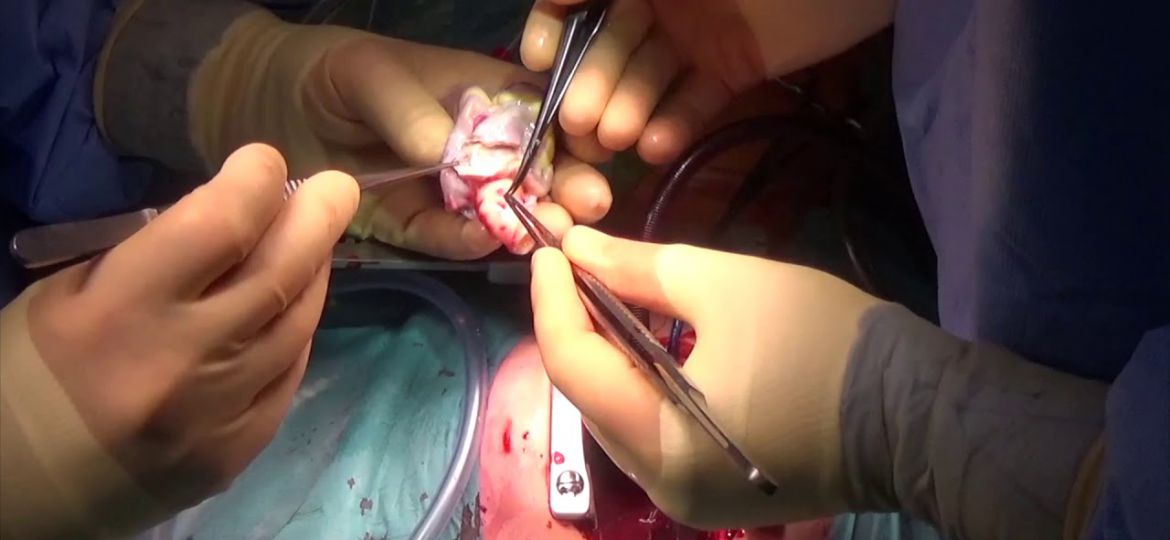

O emprego da artéria torácica interna esquerda ( AITE ) como enxerto para artéria interventricular anterior (AIA) é realizado por…

Historicamente, o desenvolvimento gradativo da cirurgia cardiovascular foi intimamente relacionado à cirurgia de revascularização do miocárdio (RM) no tratamento…